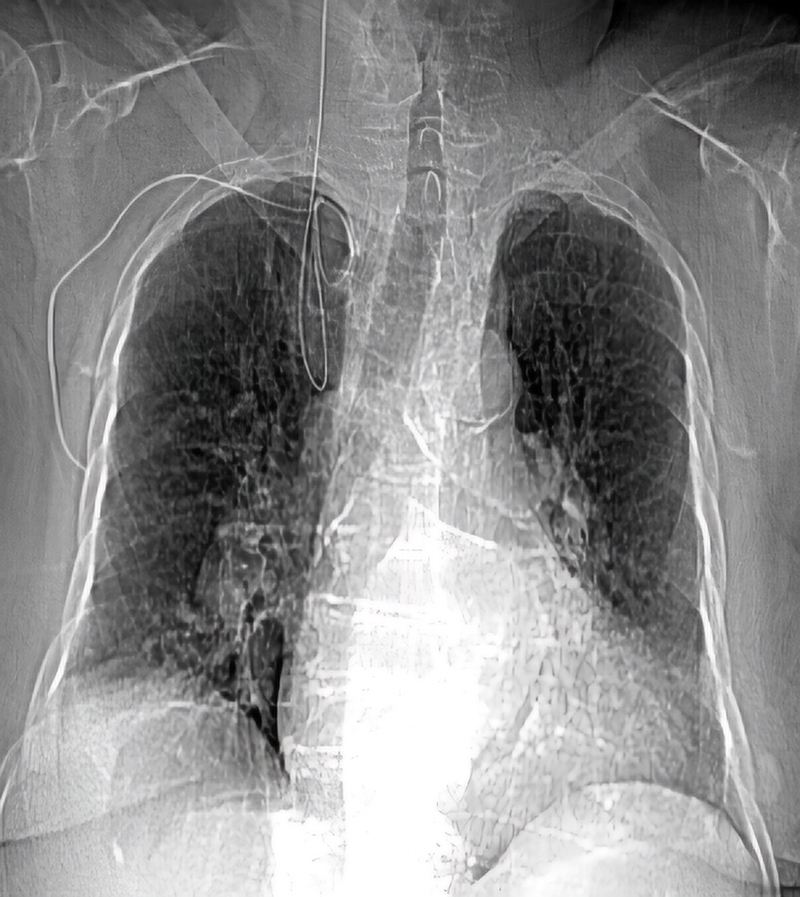

We present the case of a 79-year-old woman admitted to another hospital unit for dyspnoea at rest, fever and hypotension. The final diagnosis was community-acquired pneumonia and septic shock. Initiation of amines and placement of a right subclavian central venous catheter were required. During the procedure, resistance to the advancement of the guidewire was detected, which could not be extracted. The control X-ray revealed knotting that prevented the removal of the guidewire (figure 1), necessitating referral to the interventional cardiology service of our centre for percutaneous extraction. Prior to the decision to extract, a computed tomography (CT) with three-dimensional reconstruction was performed, which demonstrated the intravascular position of the guidewire (figure 2).